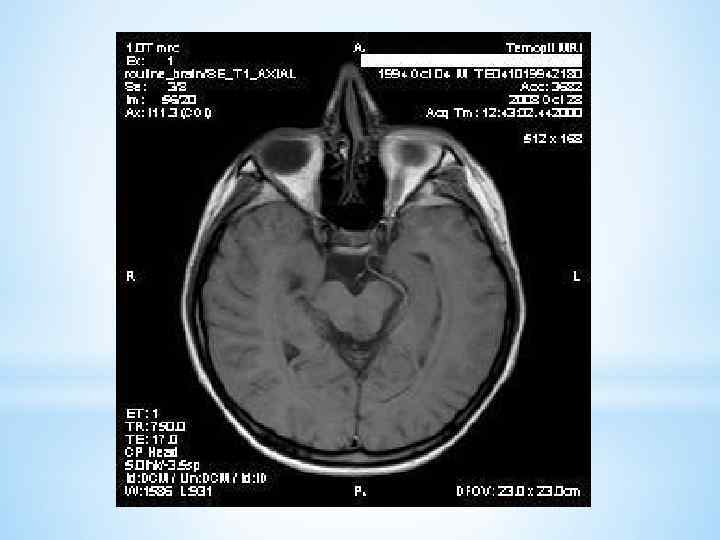

Лабораторные исследования Лабораторные методы выявляют полипсидию и полиурию, а относительная плотность мочи составляет от 1001 до 1005. Проводят пробу, исключая жидкость на протяжении трех часов. При этом низкой остается относительная плотность мочи, а осмоляльность плазмы становится выше. Если относительная плотность мочи растет, а осмоляльность плазмы в норме, это говорит о психогенной полидипсии, которая может быть у детей раннего возраста. Проводится проба с вазопрессином – 5 ЕД вводят под кожу. При абсолютной недостаточности антидуиретического гормона (что говорит о несахарном диабете) относительная плотность мочи становится выше. Если у ребенка резистентность к антидуиретическому гормону, что бывает при нефрогенном несахарном диабете, относительная плотность мочи такая же низкая. Инструментальные исследования Для диагностики необходима визуализация гипоталамо-гипофизарной области - КТ, рентгеновское исследование черепа, МРТ.